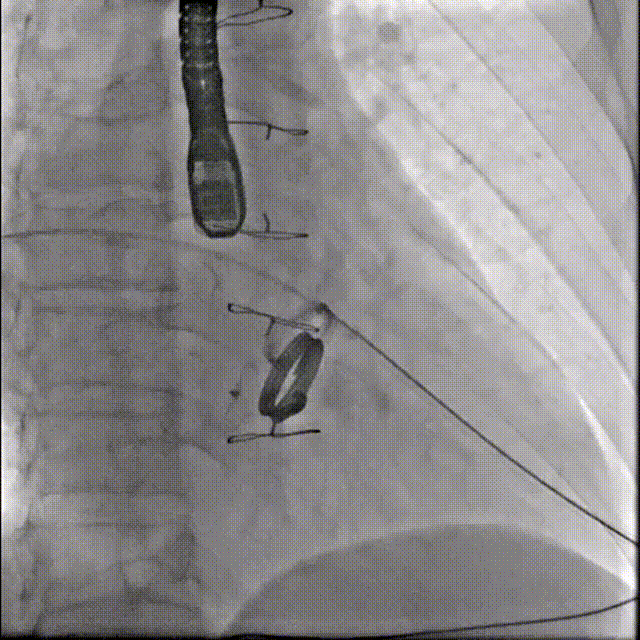

术后封堵器形态位置

手术全程顺利,术中出血100ml,使用造影剂40ml,共计用时1小时50分钟,术后患者无不适,安全返回普通病房,并于3天后出院。